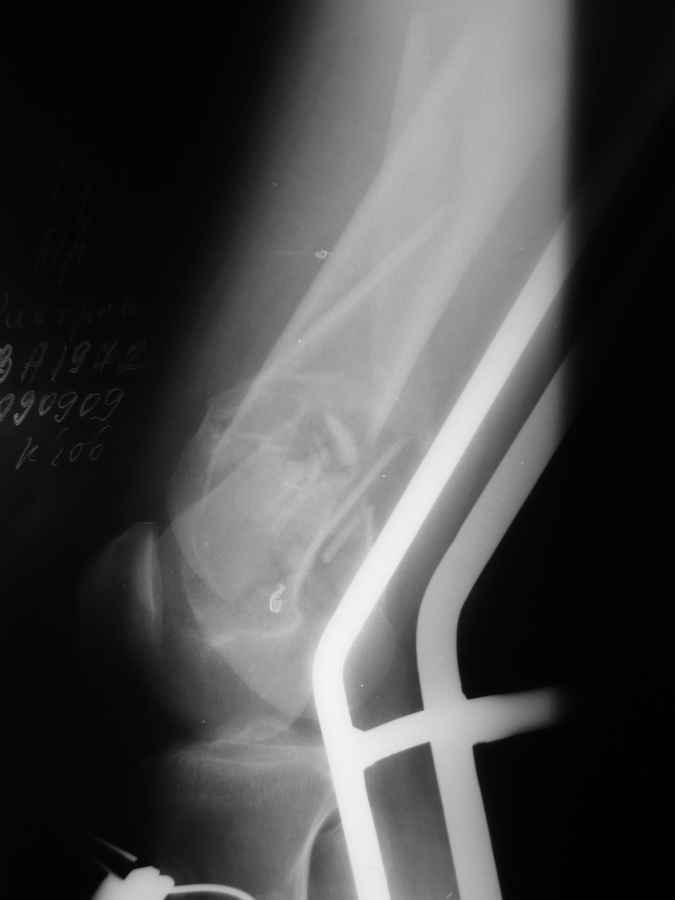

[Ortho] Дистальный перелом бедра

Вообще насчет пластины думали... но если открыться то рассыпится все... LISS можно но тоже тяжело представить...